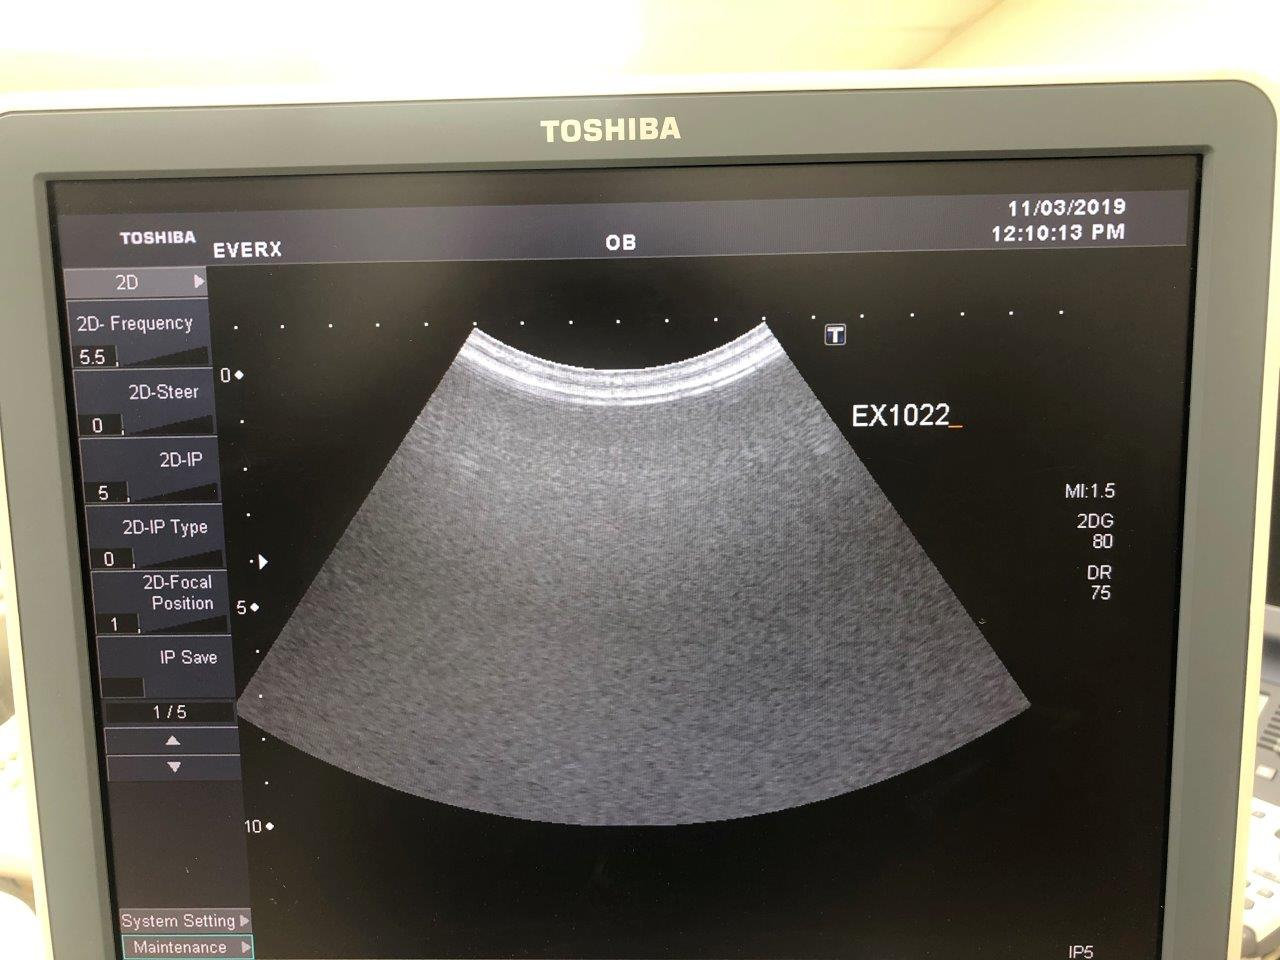

Used Toshiba Xario XG – good condition

Our Ref no. EX1020,

Multiple Probes to choose from: PVT 375BT, PVT 661VT, PLT 1204AT, PLT 704SBT